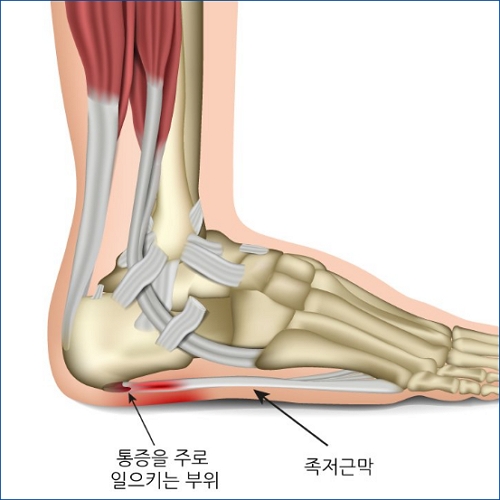

1. 족저근막염: 플랜타르 파시아염

발의 아치를 지지하는 플랜타르 파시아가 염증을 일으키는 상태로, 특히 아침에 첫 발을 내딛을 때 발뒤꿈치에 심한 통증을 유발할 수 있습니다.